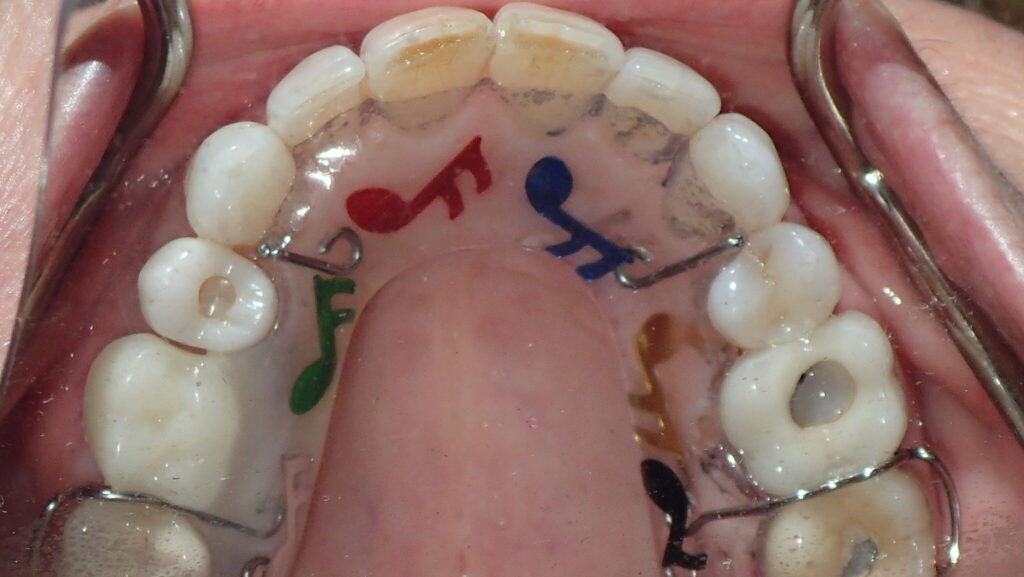

The majority of the orthodontic practices offer a period of “supervised retention” to their patients and communicates the customized retention recommendation with the patient’s general dentists. It is extremely important to work as a team to achieve long term clinical success in maintaining a functional bite and aesthetic smile. The general dentists continue to see their patients on a regular basis and have an opportunity to assess the orthodontic retainers and the bite after the supervised retention period is completed by the orthodontists. With great care, orthodontic retainers would serve for a long time (Fig. 1) without any major issues. However, in some cases, the failure to notice the clinical problems early on results in functional issues that would require a comprehensive orthodontic treatment to correct it (Fig. 2).

Fig. 1A

Fig. 1B

Fig. 1C